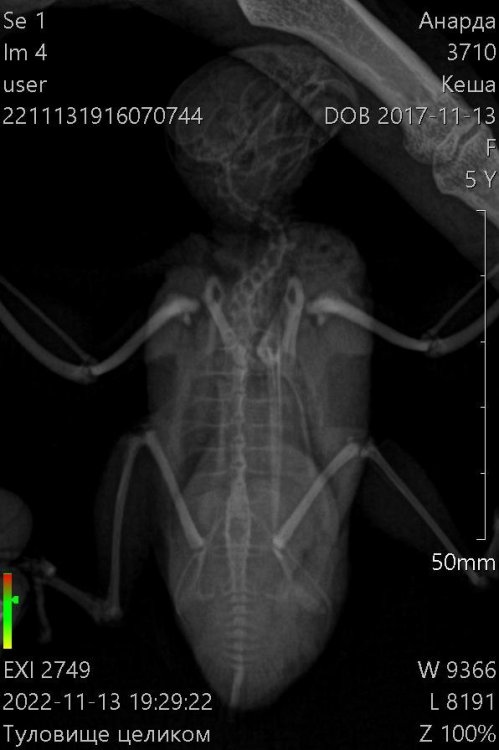

Здравствуйте! Пожалуйста, помогите моему волнистику. Больше месяца назад начались проблемы с калом. Начал какать редко и большими кучками. Сначала не придала значения, а потом у него начался сильнейший запор. Кеша перестал есть, пить, не мог вообще сходить в туалет. Орнитологов у нас нет в городе. После изучения информации на форумах, пропоила его биссептолом суспензией, кормили кашей и поили со шприца. В клюв капала вазелиновое масло. В еду линекс сыпала. Сейчас измельчаю карсил и добавляю в сухой корм. Ему стало легче, кал так и восстановился. Ходит большими кучками. Стал тяжело дышать, плохо и мало летать. На животе появилась опухоль. Сдали анализы на криптоспоридиоз и сальмонеллез- отрицательные. Сделали ренген. По результатам- проблемы с легкими и опухоль. Что делать? Умоляю, помогите!